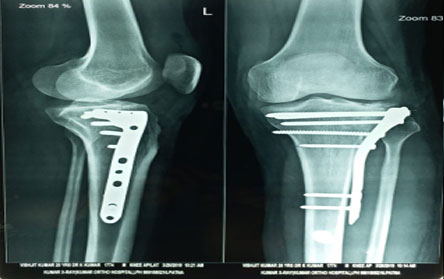

Trauma surgery:

Trauma surgery is a surgical specialty that utilizes both operative and non-operative management to treat traumatic injuries.

The Center of Orthopedics KUMAR ORTHO HOSPITAL ,Patna, offers the entire spectrum of modern orthopedic management, which is effective, patient - friendly & result oriented. In a nutshell, it is one stop treatment for all orthopedic ailments and fractures with emphasis on avoidance of complications, rapid mobilization, decreased period of confinement and an early return to normalcy.